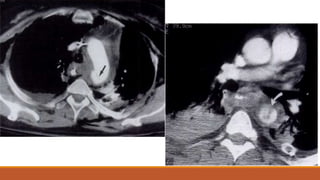

CT scan obtained at the level of the carina shows focal

narrowing of the left main bronchus that resulted

from the bronchial tear.

CT scan obtained 1 cm lower than b shows normal

diameter of the left lower lobe bronchus.